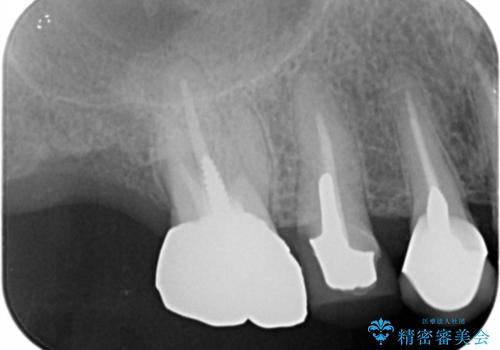

- 色や形、適合の悪いクラウンの再治療を希望され来院されました。

装着されているクラウンを除去し、自然な色調のジルコニアクラウンによる審美生の改善、インプラントを用いた欠損部の機能回復を計画します。

- 88万円(インプラント・チタンカスタムアバットメント・ジルコニアクラウン×4・仮歯×4)費用は治療当時の料金となります